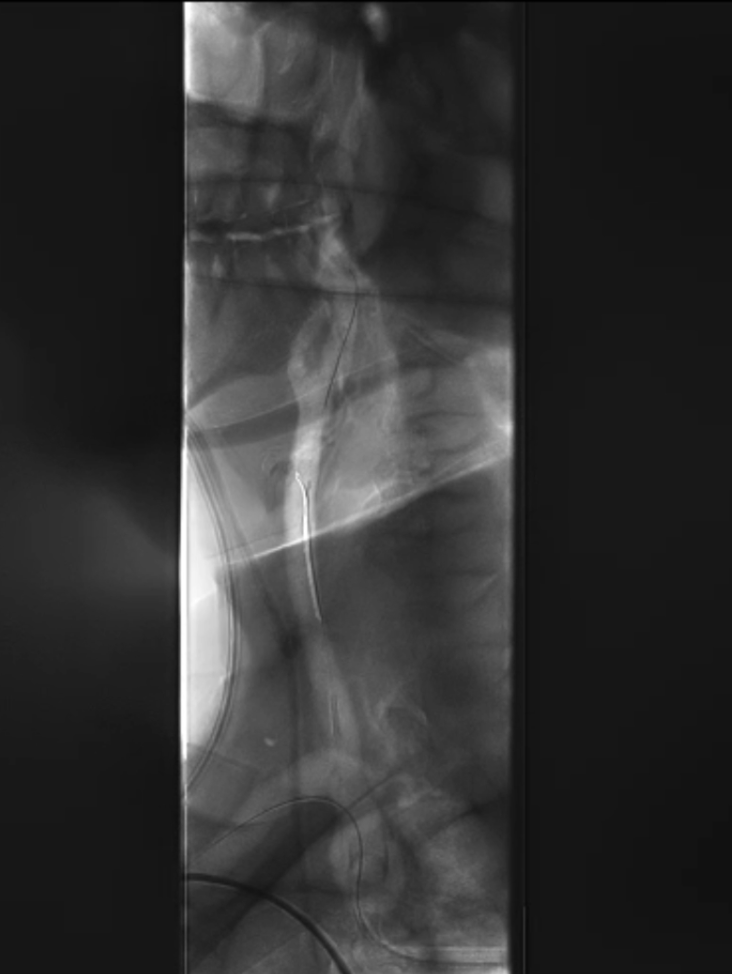

球囊扩张:采用同轴双导丝技术,以4×40mm、6×40mm球囊逐级扩张狭窄段;造影发现残存狭窄后,再次用6×40mm球囊扩张。

4*40mm球囊扩张

无名动脉支架

多角度造影

仍有残存狭窄

6*40mm球囊扩张

再次6*40mm球囊扩张

支架置入:通过“球囊带鞘”技术跟进长鞘至支架远端,采用同轴双导丝技术送入VBX8×29mm球扩覆膜支架,多角度造影定位后释放。

撤球囊时更进长鞘

至支架远端

同轴双导丝技术送入

VBX 8*29mm球扩覆膜

支架反复造影定位

释放支架